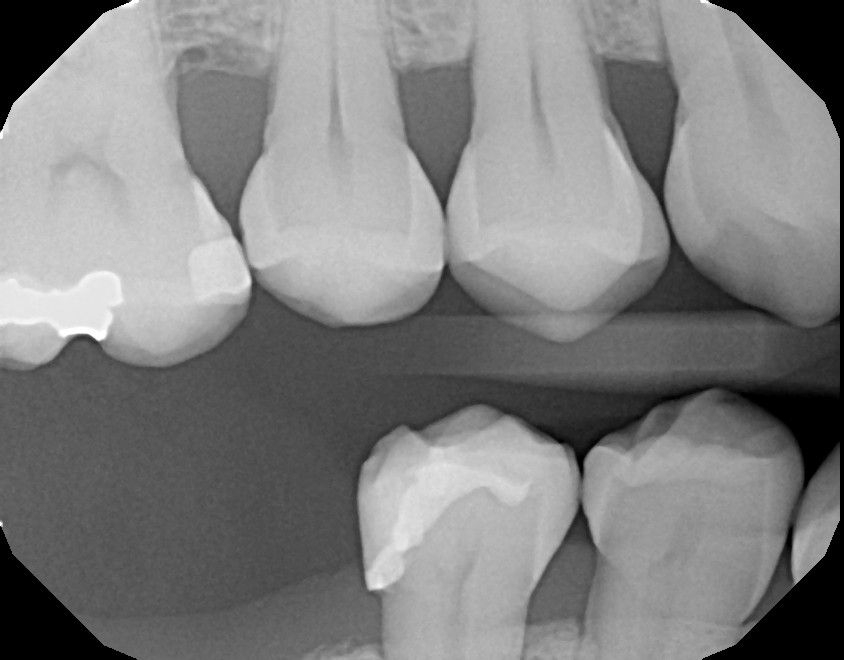

In dental radiography, CNNs help identify relevant anatomical or pathological regions like enamel, dentin, caries, or fillings, by learning hierarchical features from the input images.

Semantic segmentation goes beyond classifying an image—it labels every pixel with a category. Instead of just predicting whether a pathology is present, the model outputs a segmentation map that shows exactly where each class is located.

In practice, for dental images, this results in a single segmented mask where each region (e.g., enamel, pulp, caries) is represented by a unique color or pixel value.

These masks are typically color-coded or stored as grayscale images with predefined values (e.g., 0 for background, 1 for enamel, 2 for pulp, etc.).